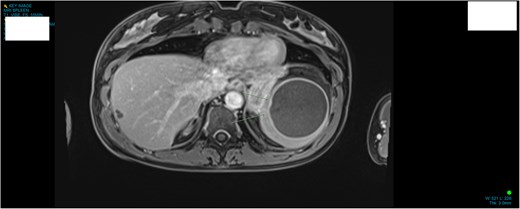

A 34-year-old woman presented to the Emergency Department with upper abdominal pain of a few days’ duration with associated nausea. She had no past medical or surgical history. She was hemodynamically stable. Routine blood work and beta human chorionic gonadotrophin were normal. Initial investigation included a Pelvic Ultrasound Scan which showed a complex cystic lesion on the superior aspect of the spleen measuring 64 × 62 × 62 mm. Further investigation with serial imaging including Commuted Tomography (CT), Magnetic Resonated Imaging (MRI) and Proton Emission Topography (PET) demonstrated a cystic lesion of the upper pole of the spleen with an enhancing mural nodule and radiological appearance of a dermoid cyst (Figs 1 and 2). This nodule was found to have low grade avidity on PET scan. The splenic vasculature demonstrated a magistral arrangement on contrast enhanced CT. Hydatid Serology was negative.

MRI demonstrating size and anatomical location of splenic lesion coronal plane.